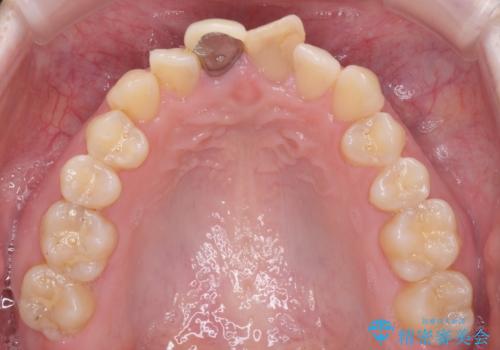

レントゲン写真より、変色してしまった歯は根管治療がされていなかったため、根管治療後にファイバーコアによる土台築製を行い、前歯2本をオールセラミッククラウンにて補綴することとしました。

変色とともに、捻れていたことも気になっていたので、その両方を解決させることとしました。